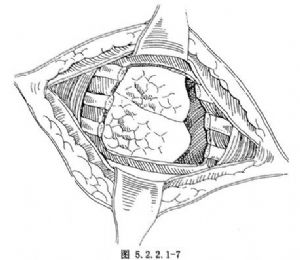

惡性腫瘤則需在腫瘤旁正常的肋間切開,伸入手指,從胸腔內探查腫瘤的範圍,連同病變上下各一根肋骨、壁層胸膜、肋間組織及該區域引流淋巴結整塊切除,兩端切斷處應距腫瘤4cm以上(圖5.2.2.1-6,5.2.2.1-7)。如病變已侵及肺表面,可做適當的肺部分切除。